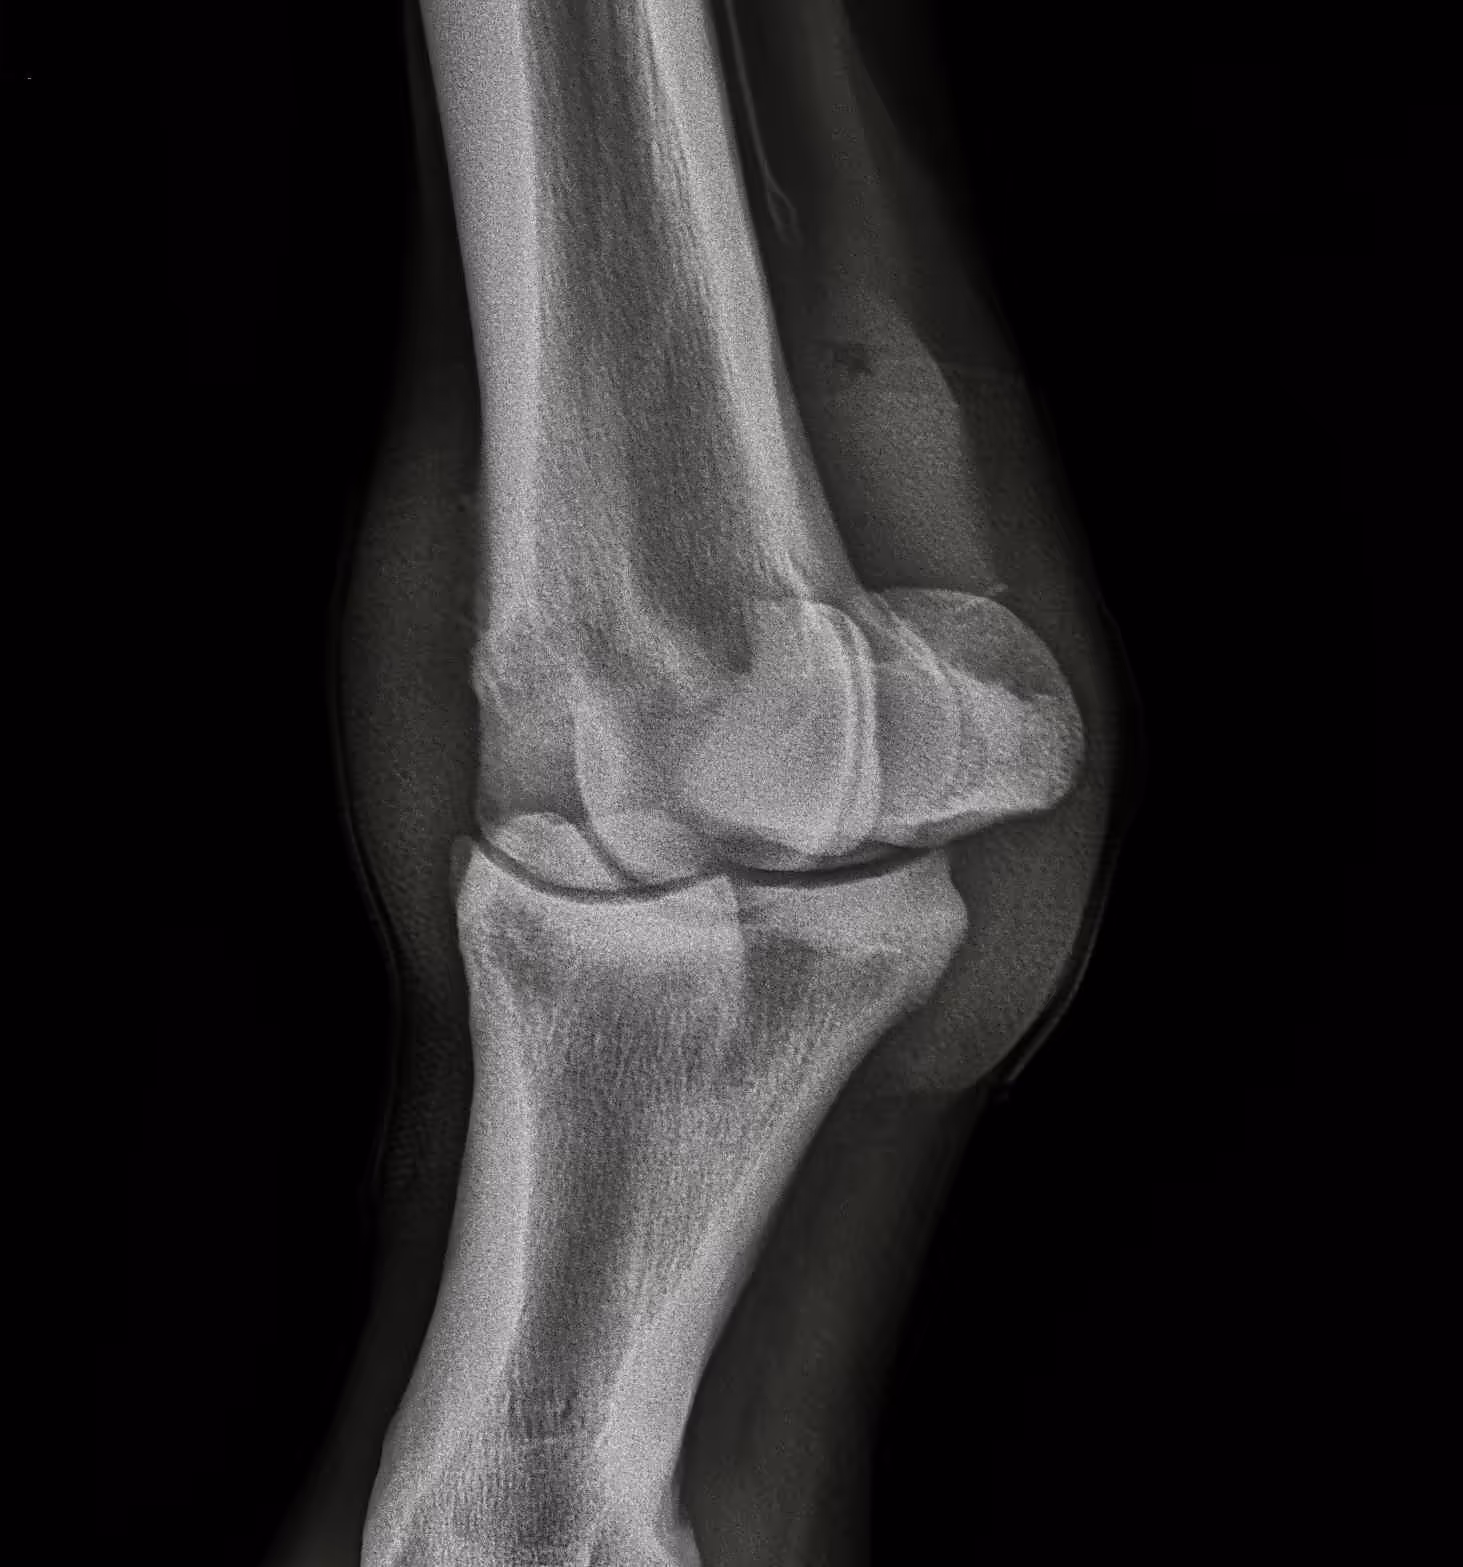

LF fetlock (LM, DLPMO, DP, DMPLO views below):

Moderate arthritis is visible as periarticular bone spurs on medial and lateral margins of P1 and MCIII. A subchondral cystic lesion is present in the medial condyle of MCIII with about 5-8mm of lost subchondral bone width. Periarticular new bone is evident at joint capsule insertions dorsally above and below the joint. Soft tissue swelling is also evident.

DMPLO (dorsomedial-palmarolateral oblique)

DLPM (dorsolateral-palmaromedial oblique)